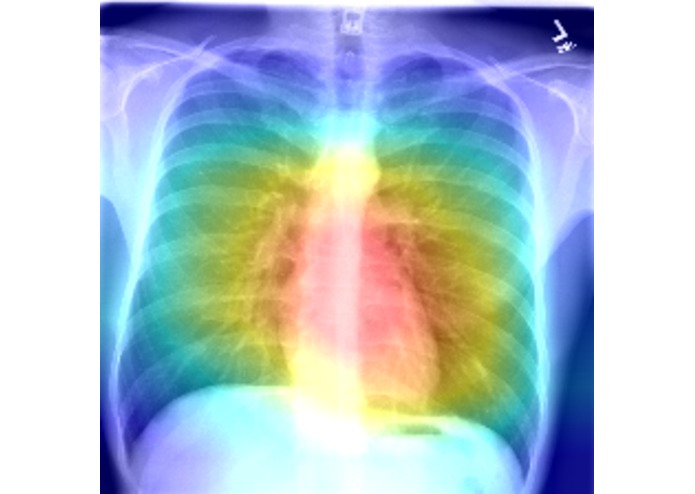

Implementation of Class Activation Maps to localize the disease visualizations on XRays. Specifically 3 different approaches and significance of each.